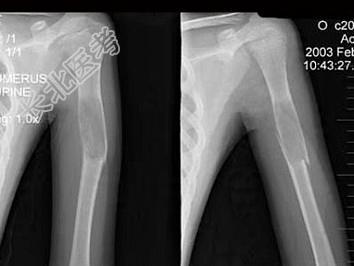

- 单项选择题13岁男性患者,因轻微外伤后感左肱骨上部疼痛, 软组织肿胀,摄片见左肱骨上段局限性骨质沿髓腔膨胀性破坏, 骨皮质变薄,部分骨皮质不连续, 最可能的诊断是  (    )

A、左肱骨骨折

B、左肱骨骨囊肿伴病理性骨折

C、左肱骨骨纤伴病理性骨折

D、左肱骨巨细胞瘤伴病理性骨折

E、以上都不正确